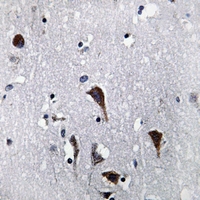

Immunohistochemical analysis of Cathepsin B staining in human brain formalin fixed paraffin embedded tissue section. The section was pre-treated using heat mediated antigen retrieval with sodium citrate buffer (pH 6.0). The section was then incubated with the antibody at room temperature and detected using an HRP conjugated compact polymer system. DAB was used as the chromogen. The section was then counterstained with haematoxylin and mounted with DPX. -